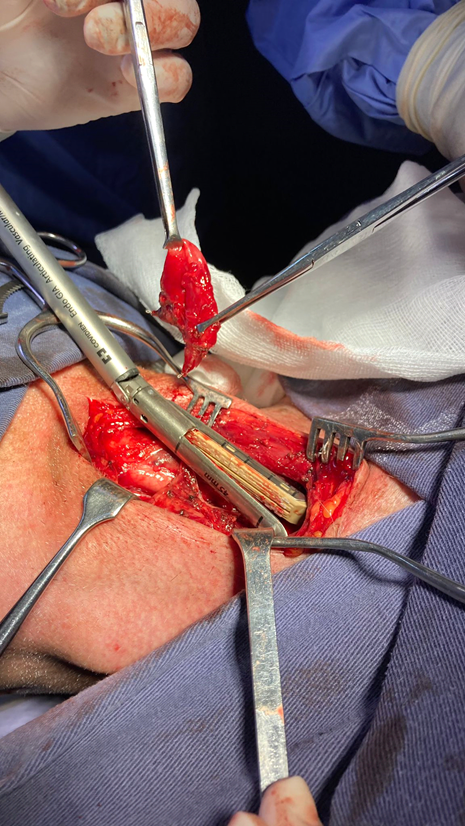

Upon reaching the neck, we can clearly identify the cricopharyngeal muscle in the lower sector, which is loaded with American forceps, taking care not to injure the mucosa and submucosa and sectioning it with ligasure or electric scalpel (Figure 7).

Figure 7 Loading of the cricopharyngeal muscle with American forceps. Once the diverticulum is completely dissected, the cricopharyngeal muscle is loaded, taking care not to injure the mucosa or sub mucosa. It is sectioned with vascular sealants.

To calibrate the esophageal lumen we use a 32 Fr chest tube. It is convenient that the placement of the probe is performed by a surgeon in continuous dialogue and coordination of the maneuver with the team that is participating in the surgery. The passage is checked visually and palpatorily a couple of centimeters distal to the neck of the diverticulum.

This passage of the 32 Fr tube allows to calibrate the esophagus avoiding the narrowing of the lumen, assuring a good passage of the alimentary bolus. Once calibrated, we are able to perform the diverticular section. The authors prefer the use of mechanical suture with triple row of hooks, violet or gold charge. The non-opening of the mucosa avoids contact of the esophageal lumen with the surrounding tissue, thus avoiding contamination (Figure 8 and 9).

Figure 8 Dissection of diverticulum up to the neck after esophageal calibration. Section with gold-loaded mechanical suture. Calibration of the esophageal lumen with a thick probe is a very important point of the surgery since it avoids narrowing the lumen and therefore postoperative dysphagia.